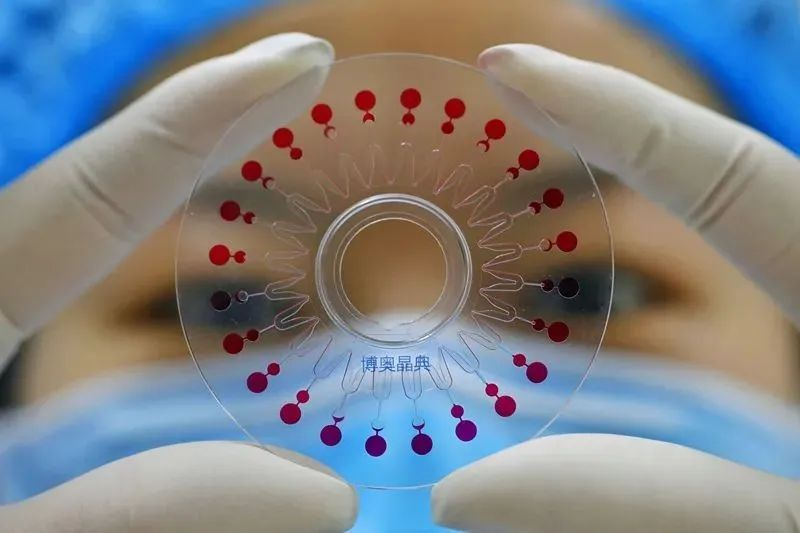

六项呼吸道病毒核酸检测试剂盒

1.5小时内出检测结果

疫情爆发时,如何能在第一时间

确定患者是否感染新型冠状病毒

那绝对离不开新型冠状的检测试剂盒

同样是受命于危难之际

博奥生物联合清华大学

和四川大学华西医院共同设计开发了

6项呼吸道病毒核酸检测试剂盒

图片来源:清华大学

这是全球首个

能在1.5小时内一次性检测

包括新型冠状病毒在内的

6项呼吸道病毒核酸检测芯片试剂盒

检测时只需采集患者的

口、咽拭子等分泌物样本

过程简单,出结果也快

这样就能快速对患者鉴别诊断

及时针对性治疗

大大减轻医院的负担

图片来源:博奥生物

对于现在疫情爆发的许多国家

他们也急需中国提供的检测试剂盒

帮助更快的筛查和确诊